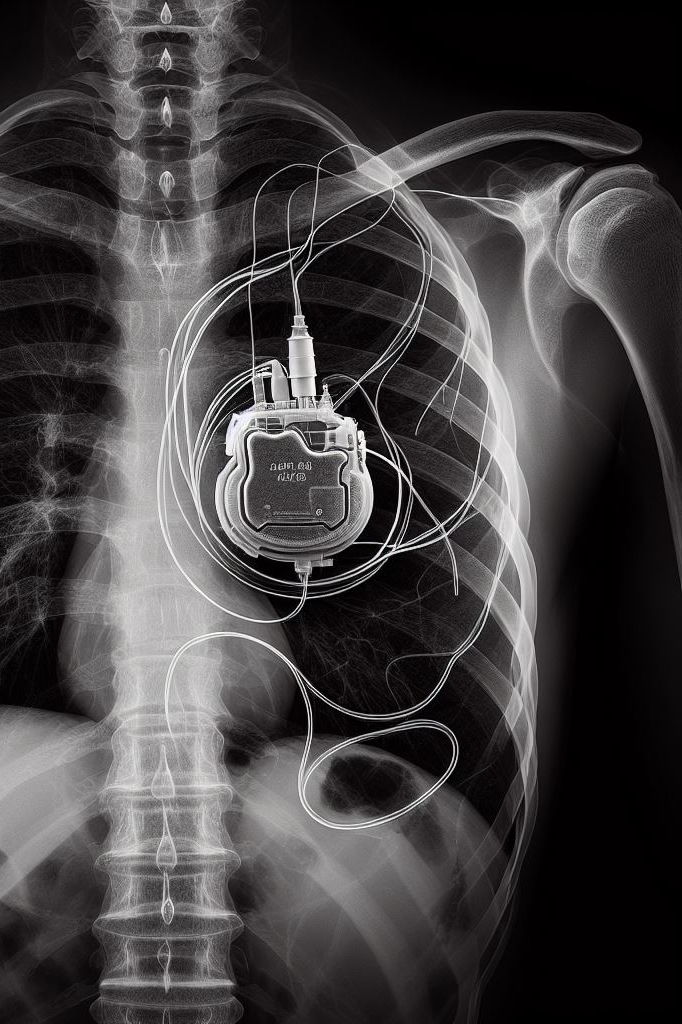

pacemaker

Negli ultimi anni, l’impiego della tecnologia in ambito medico è cresciuto enormemente, in particolare nello sviluppo e nell'utilizzo di dispositivi medici impiantabili attivi (DMIA). Questi dispositivi, che vanno dai pacemaker ai defibrillatori impiantabili, agli stimolatori neuronali e agli impianti cocleari, hanno rivoluzionato il trattamento e la gestione di molte patologie. Tuttavia, accanto agli indubbi benefici che queste tecnologie hanno prodotto, è importante considerare anche i pericoli che possono derivare da un loro non corretto funzionamento, come, ad esempio, quelli derivanti dall’esposizione a campi elettromagnetici. L’interferenza elettromagnetica (EMI), infatti, può causare malfunzionamenti nei DMIA, con conseguenze gravi per i pazienti, per i quali spesso ricoprono un ruolo salva-vita. Ad esempio, l'interferenza con un pacemaker o un defibrillatore impiantabile potrebbe causare episodi di stimolazione inappropriata, la mancata erogazione della terapia necessaria o addirittura l'insorgenza di aritmie potenzialmente letali.